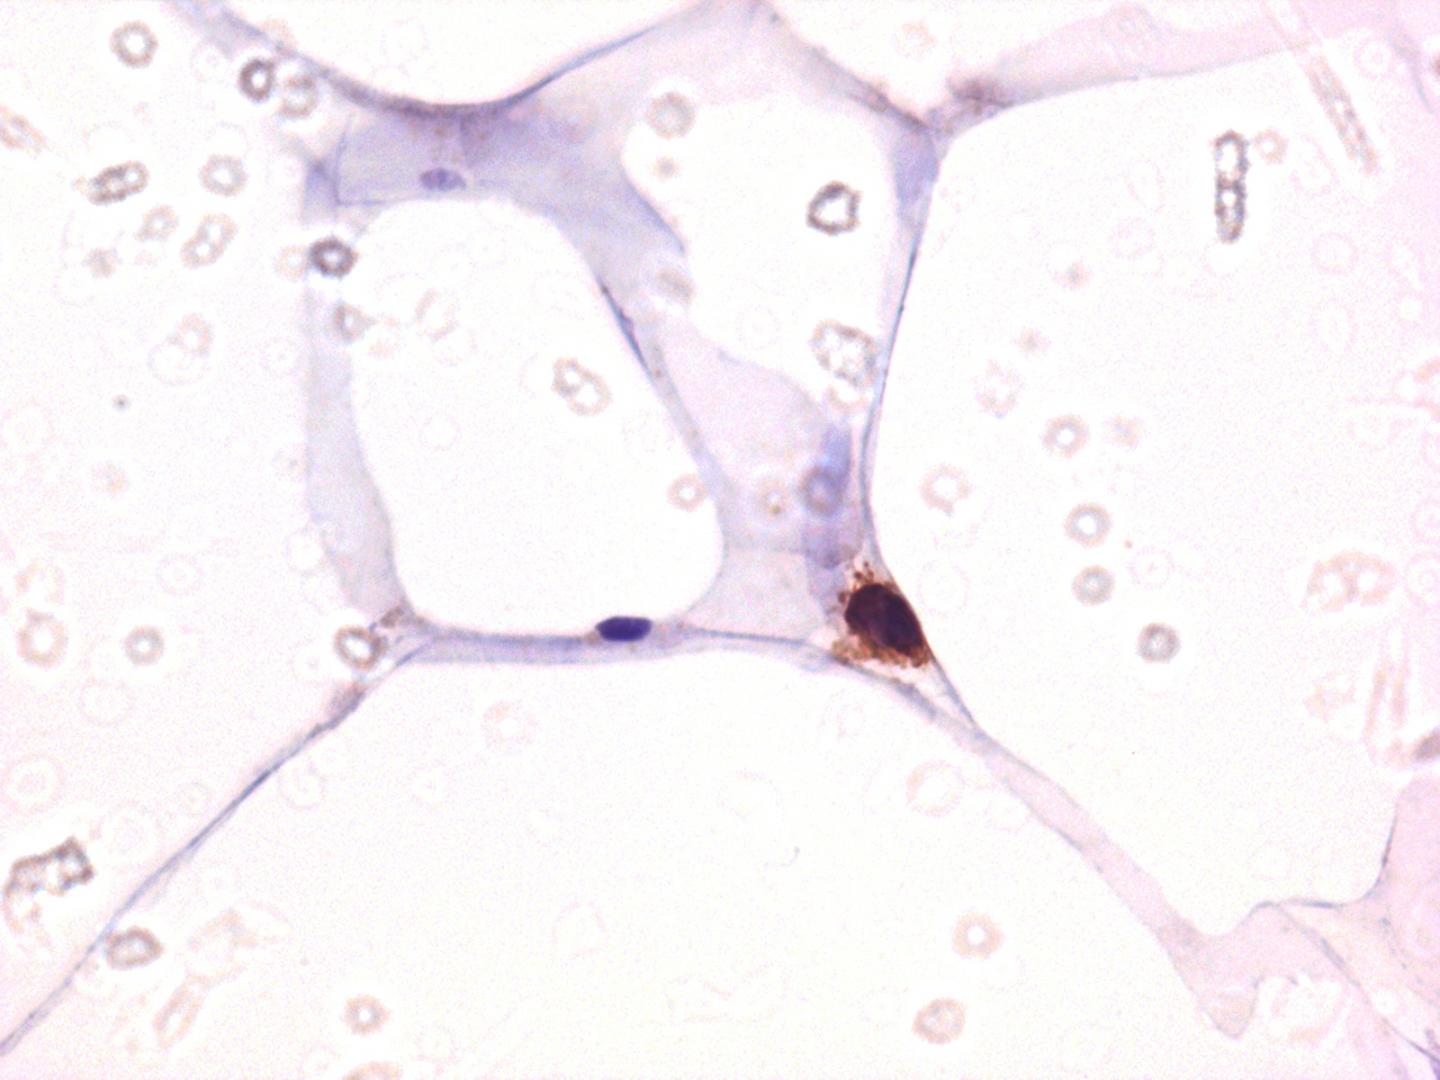

Caption:

CD4 staining among adipose tissue demonstrating that the main target of HIV, i.e. CD4 T cells, is indeed detectable in adipose tissue. CC-BY Damouche et al.